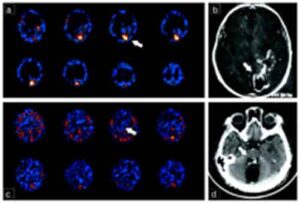

Alcuni scienziati tedeschi hanno perfezionato e utilizzato un metodo per osservare l'elaborazione delle informazioni visive da parte delle singole cellule...